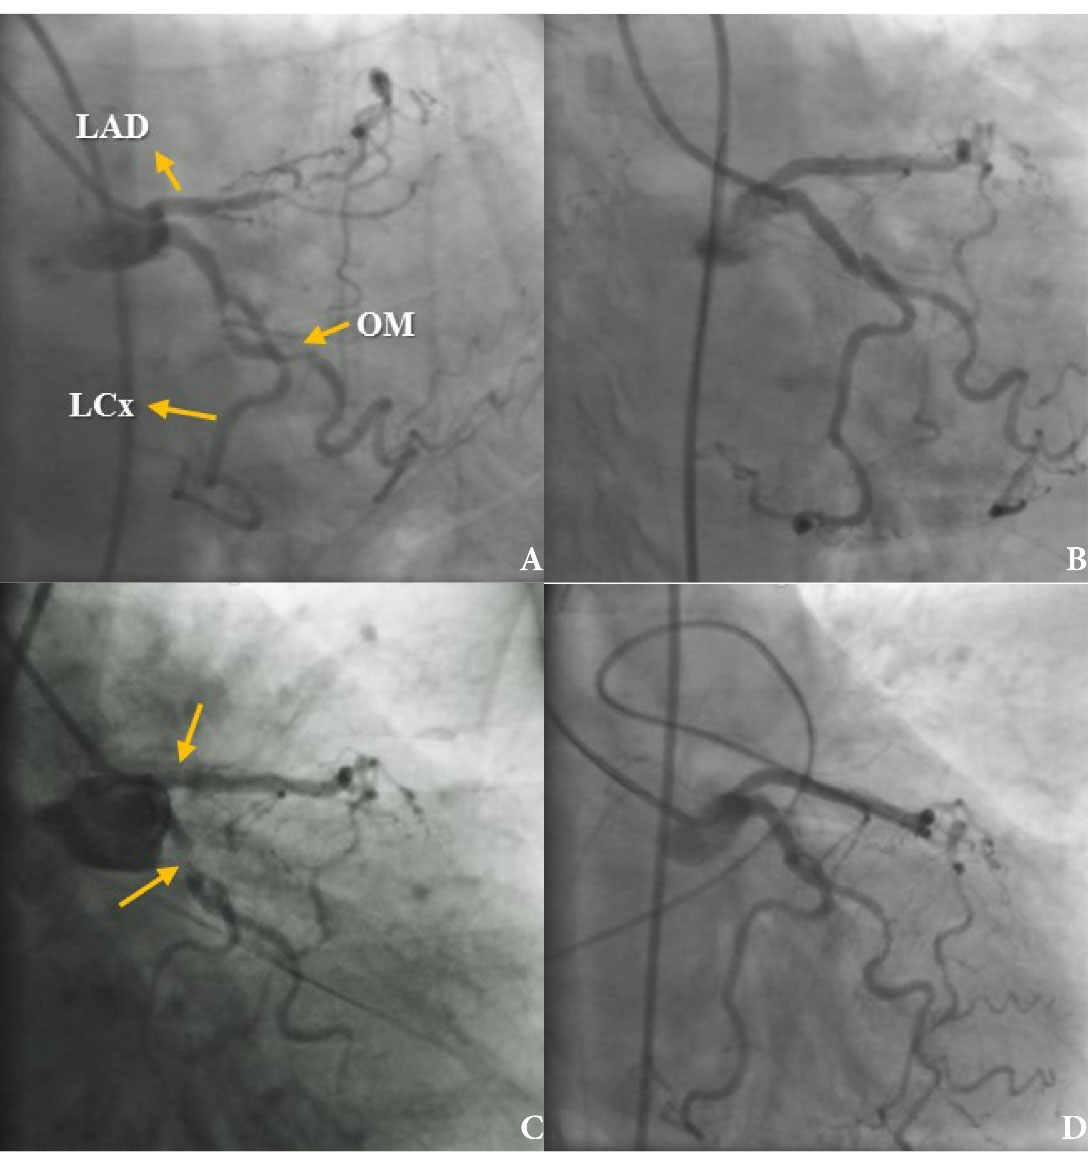

A 73-year-old diabetic woman presented with chest pain and dynamic ST elevation in electrocardiogram and positive troponin. The patient was referred from another center for catheterization because she had recurrent angina and did had not consent to undergo Coronary Artery Bypass Surgery (CABG). Electrocardiogram in our hospital showed ST depression and T inversion in precordial leads. Angiography was performed which showed severe stenosis in Left Circumflex (LCx) and Left Anterior Descending artery (LAD). Also, there was no Right Coronary Artery (RCA) and LCx was dominant (). The drug-eluting stents were implanted into LCx and LAD. Complete reperfusion was achieved in the standard technique PCI (). Her vital sign was stable and had sinus rhythm in monitoring. Echocardiography was normal. She was transferred to the coronary care unit.

Figure 1.

(A) Right anterior oblique (RAO) caudal view revealing a dominant left circumflex artery (LCX); several significant narrowing in LCX, obtuse marginal artery (OM), and left anterior descending (LAD); (B) After first percutaneous coronary intervention (PCI): implanted stent in left anterior descending (LAD) and left circumflex artery (LCx) to the obtuse marginal artery (OM), that showing these vessels were patent; (C) Coronary angiography revealing a large thrombus in the left circumflex artery (LCx) and left anterior descending (LAD); (D) reperfusion was performed successfully, again.

Approximately 20 min after PCI, the patient developed chest pain and electrocardiogram monitoring showed ST elevation and 2:1 AV block. The patient was transferred immediately to the catheterization laboratory, where suddenly cardiac arrest occurred. Angiography and Cardiopulmonary Resuscitation (CPR) were performed simultaneously and pacemaker was implanted. Both stents of LCx and LAD formed thrombus, and LCx showed total occlusion (), and another time reperfusion was achieved through PCI (). Femoral access was used for both procedures. Eptifibatide was administered (180 mcg/kg IV stat, then continuous infusion 1 mcg/kg/min with another 180 mcg/kg IV bolus 10 minutes after 1st one). After CPR, the patient was admitted in the intensive care unit where hydration with N/S and dopamine infusion started.